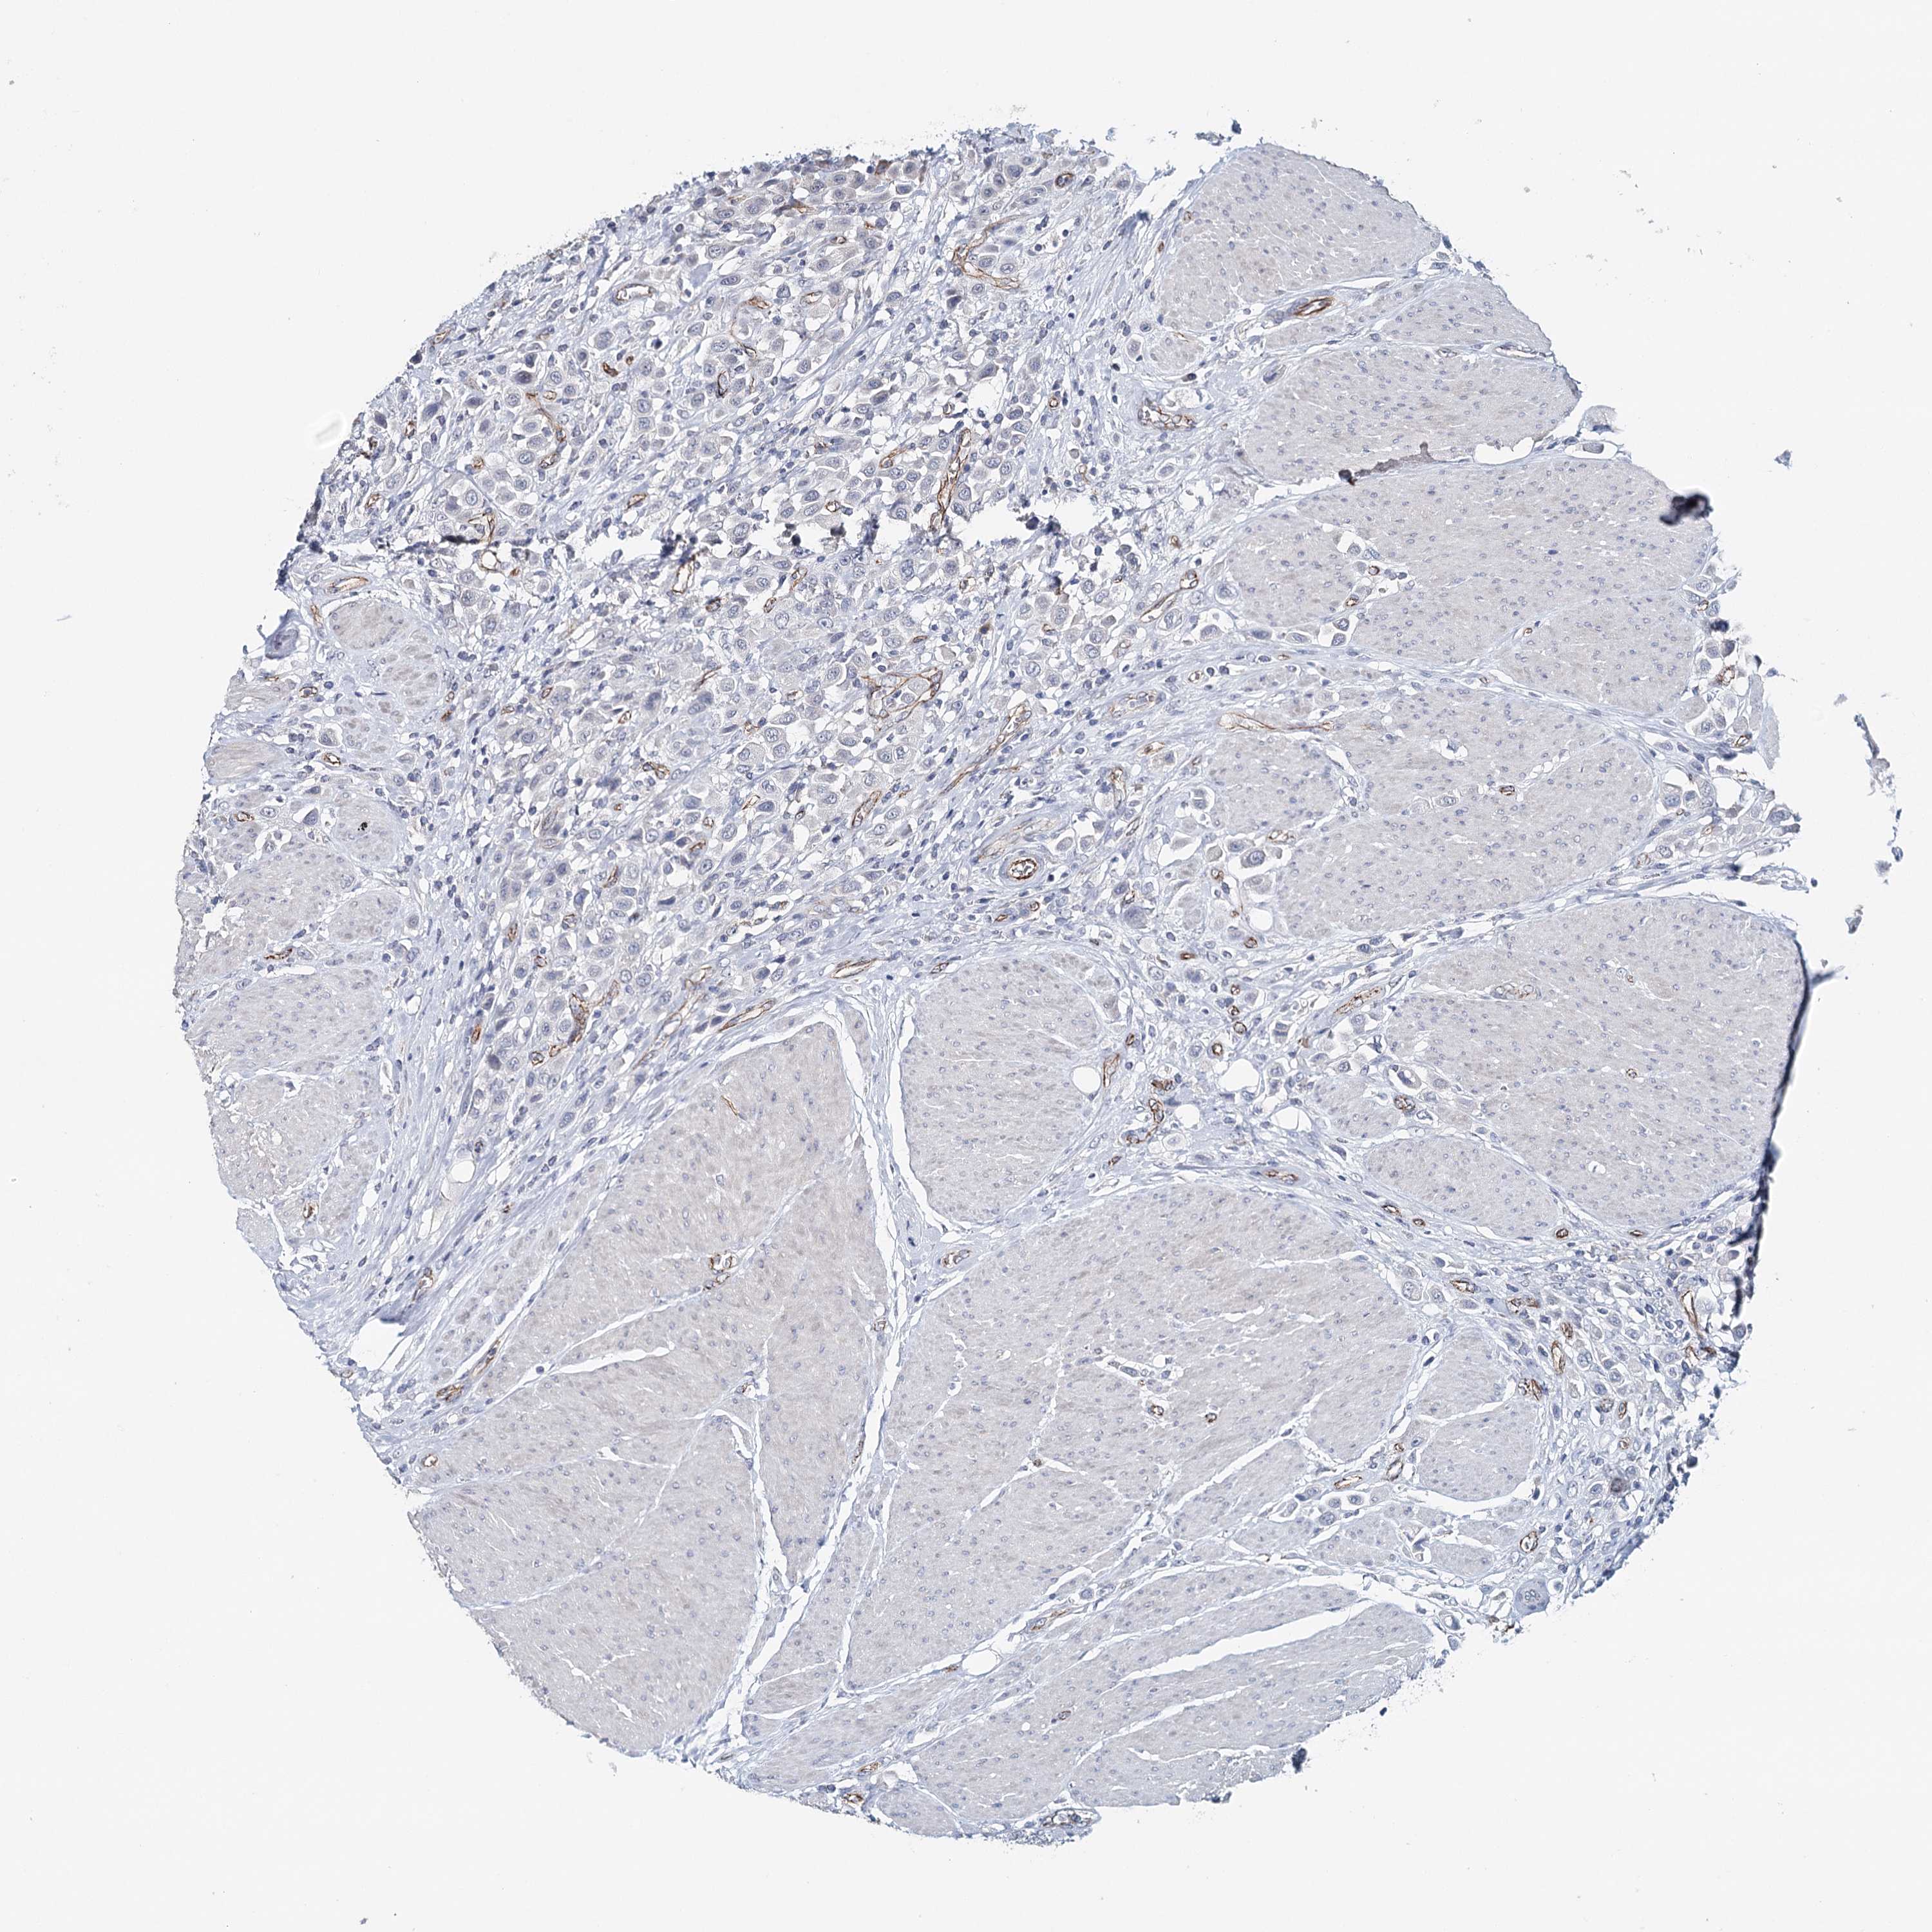

UROTHELIAL CANCER - Protein expressioni

A mouse-over function shows sample information and annotation data. Click on an image to view it in a full screen mode. Samples can be filtered based on level of antibody staining by selecting one or several of the following categories: high, medium, low and not detected. The assay and annotation is described here.

Antibody stainingi

Antibody staining in the annotated cell types in the current human tissue is reported as not detected, low, medium, or high, based on conventional immunohistochemistry profiling in selected tissues. This score is based on the combination of the staining intensity and fraction of stained cells.

Each image is clickable and will lead to virtual microscopy that enables deeper exploration of all samples and also displays staining intensity scores, fraction scores and subcellular localization as well as patient and tissue information for each sample.

Antibody HPA034631

Antibody HPA071347

Antibody CAB033265

Antibody CAB037325

Urothelial carcinoma, High grade

Urothelial carcinoma, Low grade

Urothelial carcinoma, NOS